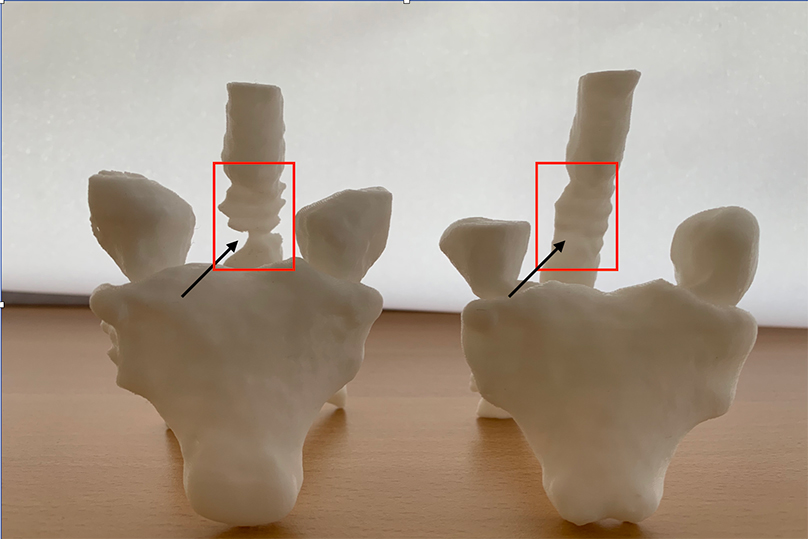

Η αντιμετώπιση των παραμορφώσεων της σπονδυλικής στήλης των ενηλίκων, ένα πολύ ιδιαίτερο και δύσκολο χειρουργικό πρόβλημα, βασίζεται πλέον στον ακριβή, γεωμετρικό, τρισδιάστατο προεγχειρητικό σχεδιασμό, με τη βοήθεια υπολογιστικών προγραμμάτων χειρουργικού σχεδιασμού. Μέσω αυτής της τεχνικής, σχεδιάζεται με απόλυτη ακρίβεια η χειρουργική επέμβαση ενώ παράλληλα προκατασκευάζονται και υπάρχουν διαθέσιμα στο χειρουργείο τα εξατομικευμένα, διαφορετικά για κάθε διαφορετικό ασθενή, υλικά σπονδυλοδεσίας.

Διεγχειρητική τρισδιάστατη απεικόνιση σε πραγματικό χρόνο (ρομποτική χειρουργική), για την ασφαλή και ακριβή τοποθέτηση των χειρουργικών υλικών σπονδυλοδεσίας (α), αντιμετώπισης όγκου στον αυχένα - σπονδυλοσπλαστική (β, γ), και οστικής μετάστασης στη λεκάνη - θερμική εκτομή του όγκου με ραδιοσυχνότητες(δ)